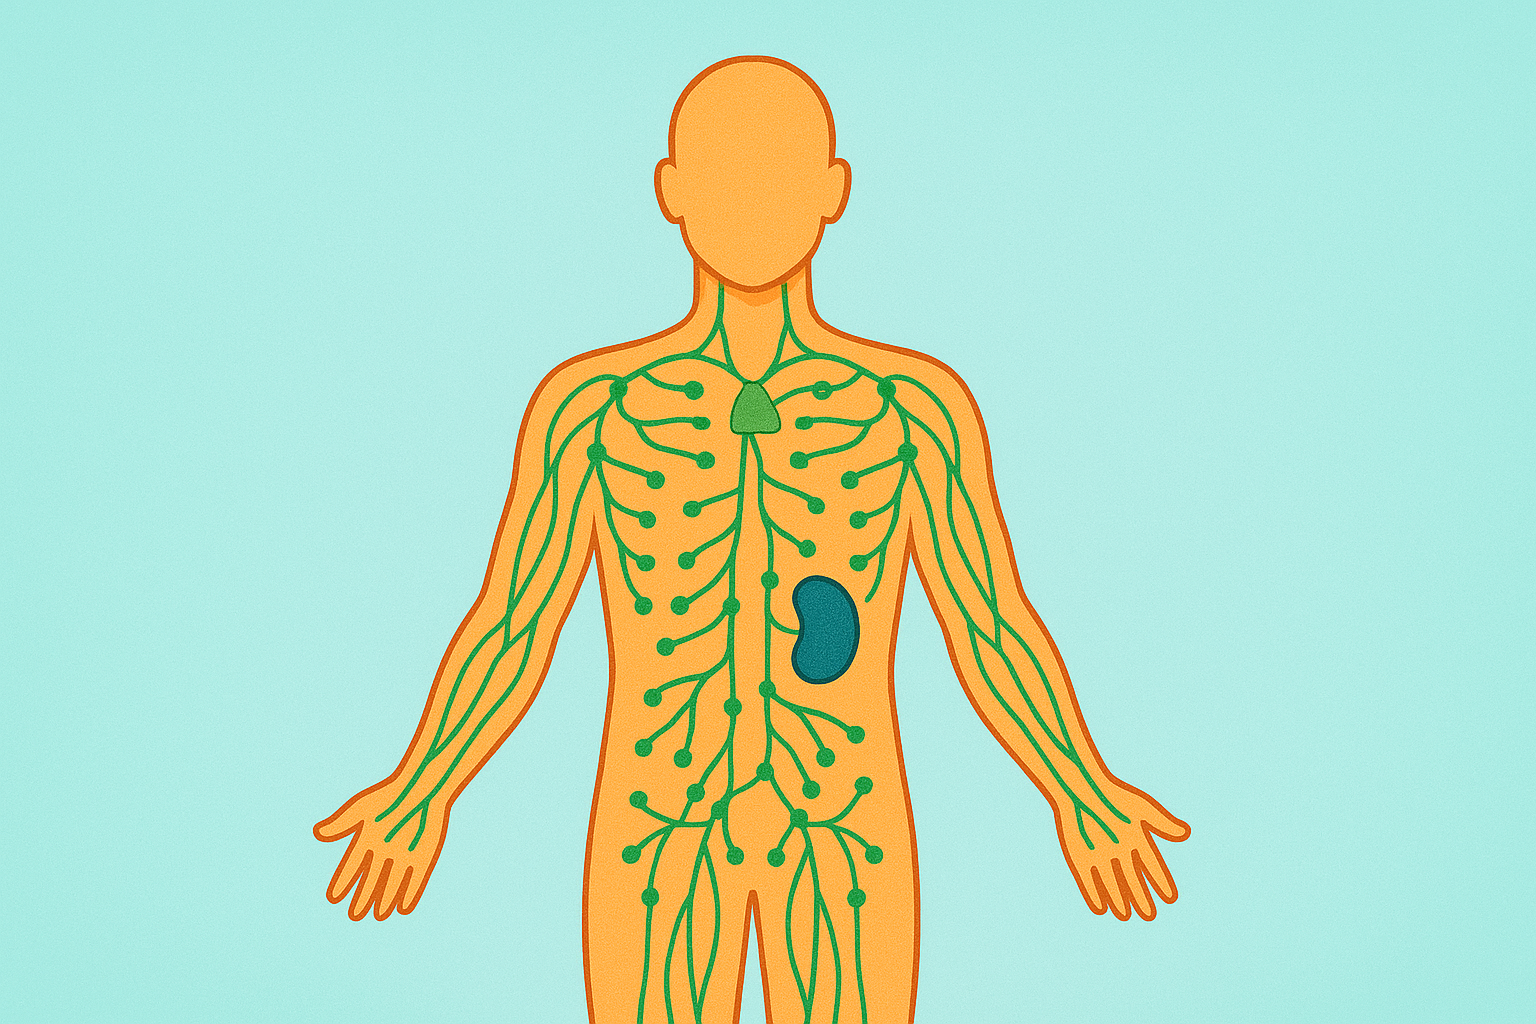

Niveau 1: Anatomie et Physiologie

Formation de 184 heures en anatomie, physiologie et introduction à la pathologie (APP).

Une immersion progressive dans l’organisation du corps humain, ses mécanismes fondamentaux et les bases de la compréhension des maladies.

Programme reconnu par l’ASCA (cycle 1), la RME et l’OrTra TC.